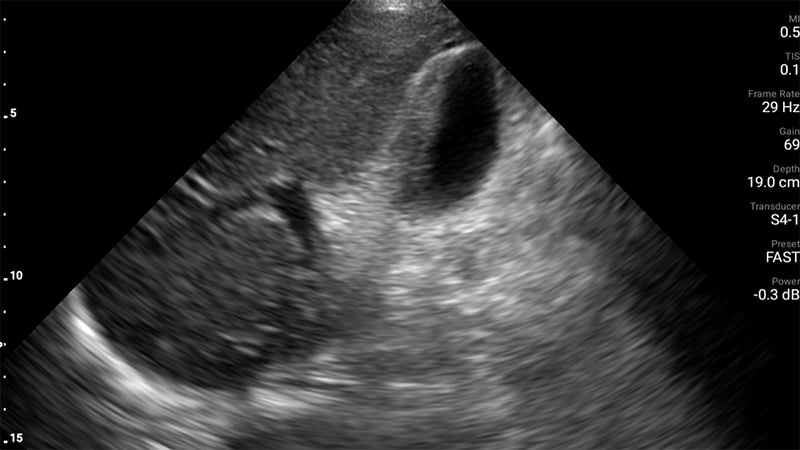

Figures 24B & 24C. Large pyogenic liver abscess with heterogenous material swirling inside the lesion, measuring >11cm in the long dimension (B) and >5cm in the shorter dimension (C).